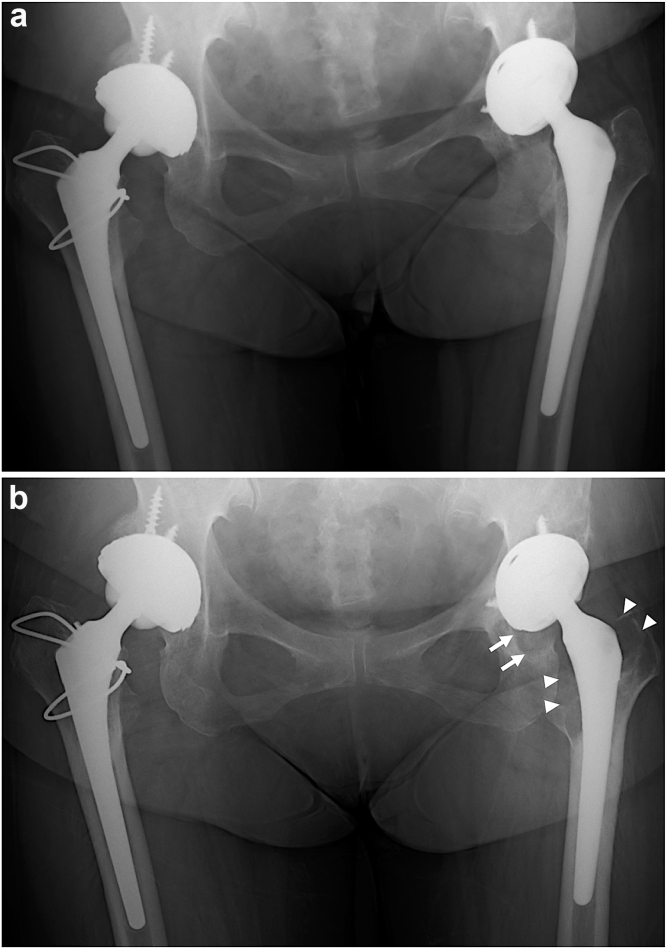

Figure 1.

(a) Six-year postoperative anteroposterior (AP) pelvic radiograph showing an early stage of femoral osteolysis in Gruen zones 1 and 7 and acetabular osteolysis in DeLee and Charnley zone 3 in the left hip. (b) Ten-year postoperative AP pelvic radiograph showing progressive femoral (arrowheads) and acetabular (arrows) osteolysis in the left hip.